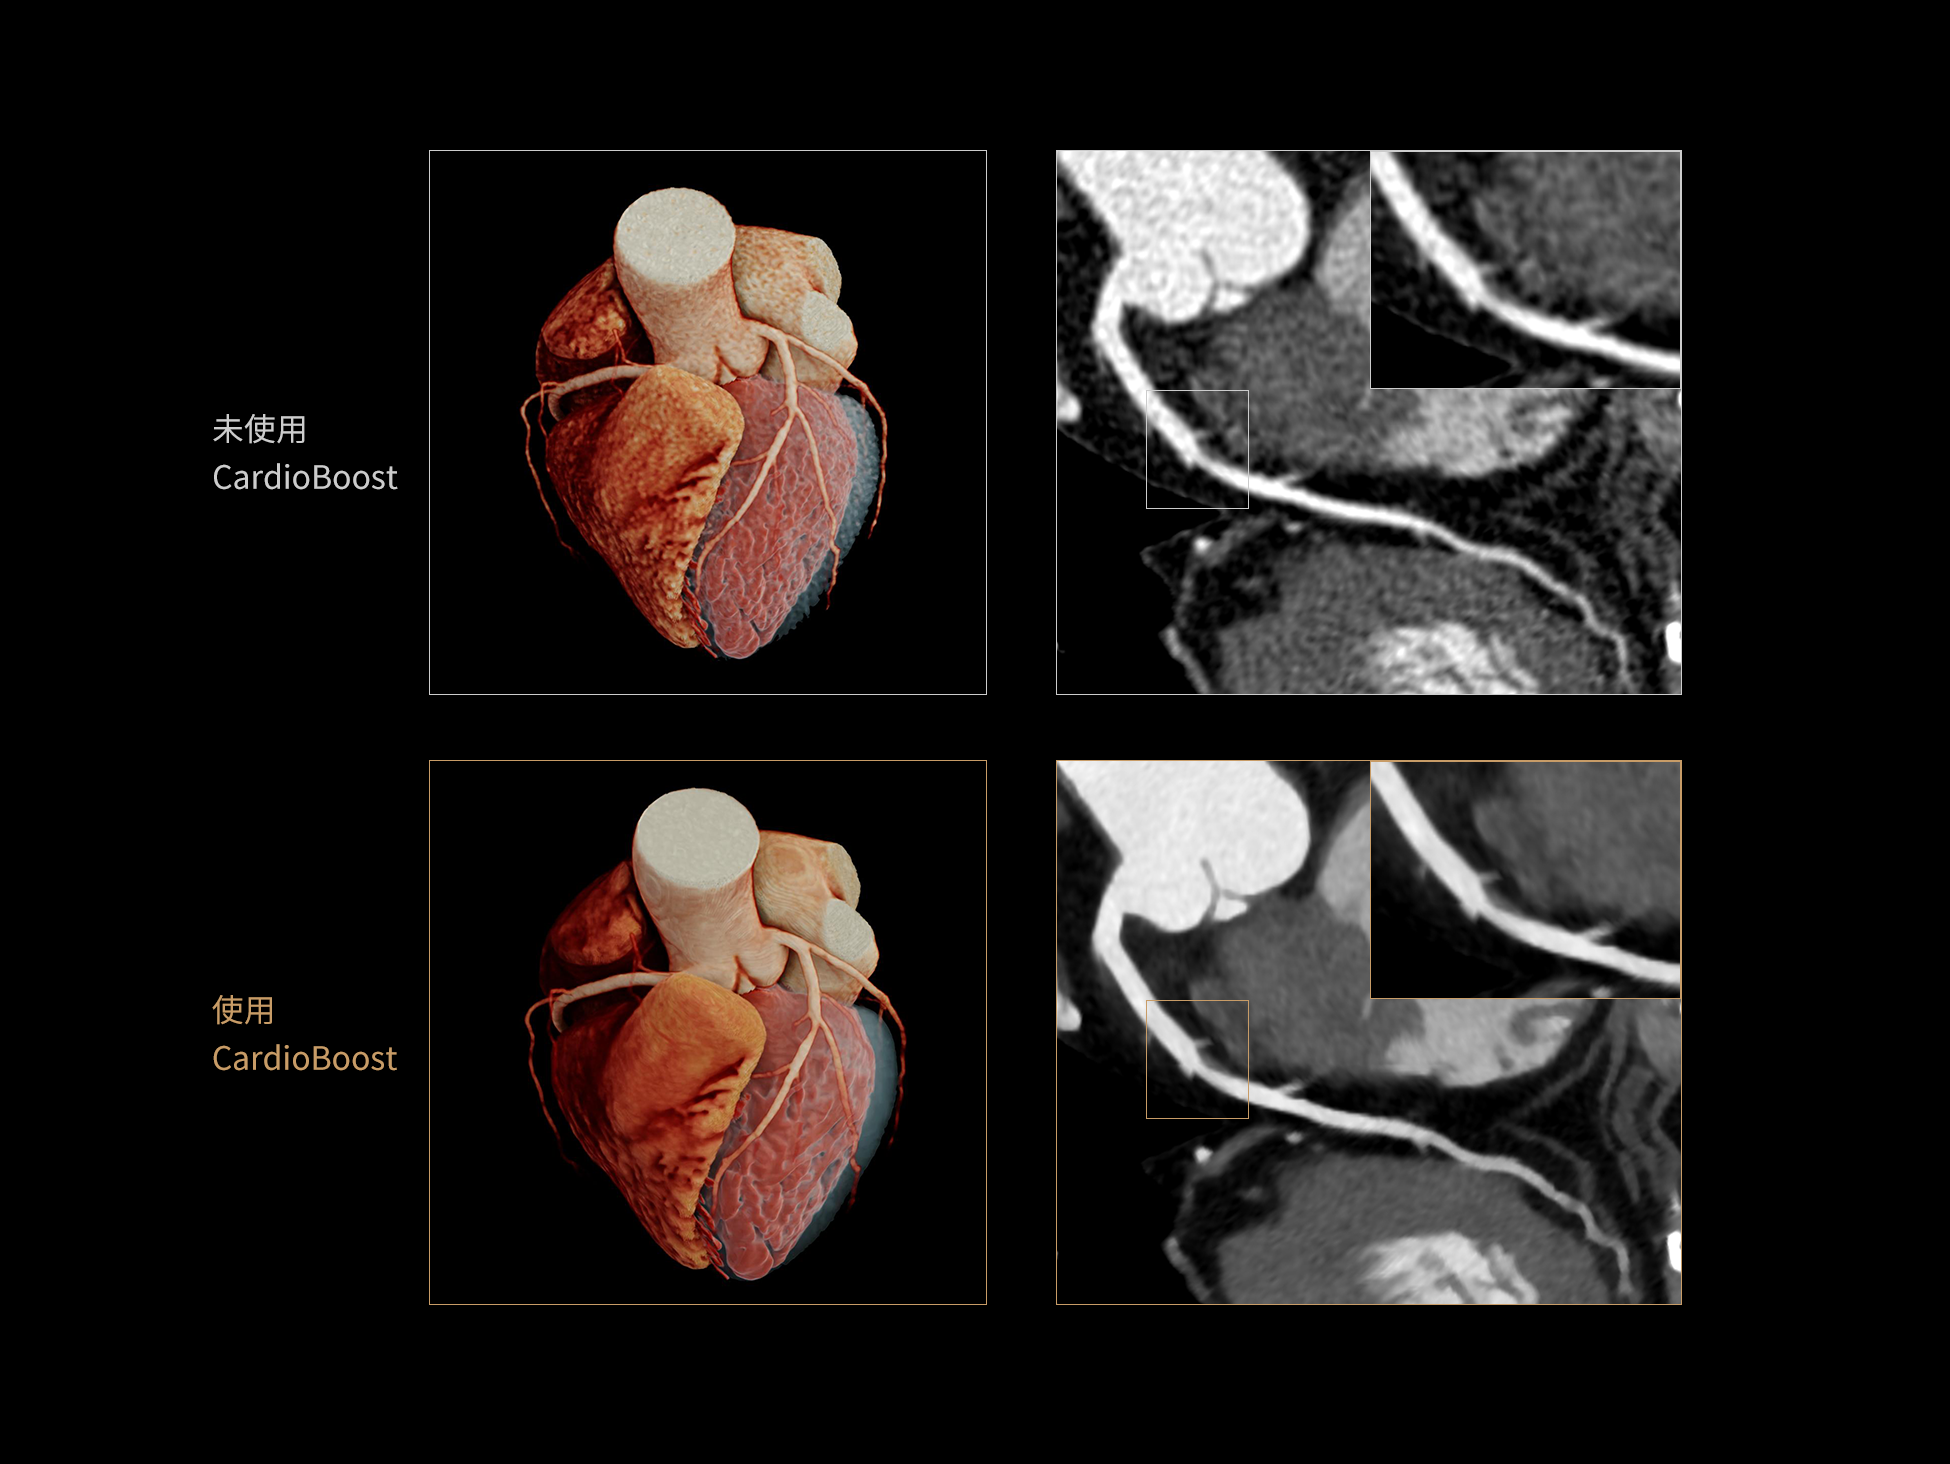

CardioBoost:专属网络设计,重塑心脏影像表现

目前心脏的 CT 检查还存在辐射剂量偏高、空间分辨率不足、 致密钙化伪影影响冠脉狭窄程度评估等方面的限 制[1][2]。CardioBoost 技术专为心脏 CT 高清成像而开发,通过 3D 神经网络的深度学习技术,利用先进的注意力机制在识别关键成像特征方面的出色表现,能够精确地聚焦于斑块、支架以及微小血管等关键细节,清晰展示这些结构与冠脉血管的边界,从而显著提高诊断的准确性,并提升医生的诊断信心。创新的 CardioBoost 心脏图像重建算法,不仅实现了图像清晰度的提升和伪影的去除,更能在减少辐射剂量的同时,保证心脏图像的高质量和图像纹理的自然。

采用 3D 神经网络的空间结构优势与精细的组织分类能力,CardioBoost 技术优化了组织对比,高清展示血管斑块,使斑块与血管边缘的轮廓清晰可辨,提升斑块诊断与评估的精确性。

借助 3D 神经网络设计、空间注意力机制聚焦与特征强化作用,CardioBoost技术提升图像的空间分辨率,实现冠脉支架的高清成像,对支架形态与管腔通畅度的评估更精准。

CardioBoost 整合先进的 3D 神经网络和空间注意力机制,大幅增强数据处理的速度与精确度。该技术能有效抑制由致密钙化引起的晕状伪影,清晰展现钙化斑块的原始结构和大小,对冠脉狭窄的评估更加精确可靠。